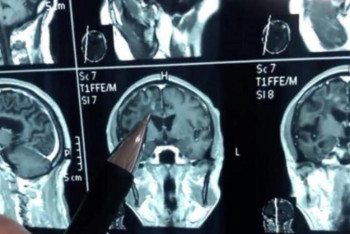

Қытай тұрғынының миында 30 жыл бойы құрт болған

Нұр-Сұлтан, BAQ.KZ. 1989 жылдан бастап ер адамның басы ауырып, эпилепсиясы ұстап қалатын болған. 2019 жылда ғана оның миынан 10 сантиметрлік құрт алынды.

Елбасы кеншілерді Шахтер күнімен құттықтадыНұр-Сұлтан, BAQ.KZ. Қазақстанның Тұңғыш президенті – Елбасы Нұрсұлтан Назарбаев кеншілерді Шахтер күнімен құттықтады.24.08.20196520![]() Қытай тұрғынының миында 30 жыл бойы құрт болғанНұр-Сұлтан, BAQ.KZ. 1989 жылдан бастап ер адамның басы ауырып, эпилепсиясы ұстап қалатын болған. 2019 жылда ғана оның миынан 10 сантиметрлік құрт алынды.24.08.20192908

Қытай тұрғынының миында 30 жыл бойы құрт болғанНұр-Сұлтан, BAQ.KZ. 1989 жылдан бастап ер адамның басы ауырып, эпилепсиясы ұстап қалатын болған. 2019 жылда ғана оның миынан 10 сантиметрлік құрт алынды.24.08.20192908![]() 24 тамызға арналған ауа райы болжамыНұр-Сұлтан, BAQ.KZ. "Қазгидромет" РМК синоптиктері сенбі күні елімізде қандай ауа райы болатынын болжады.24.08.20192107